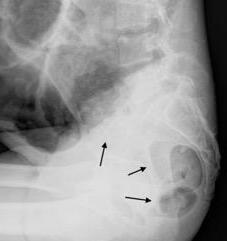

Diafragma “colgante” (“dangling sign”)

(“Dangling sign”)

Diafragma discontinúo Herniación de la grasa omental

Desser TS et al.The dangling diaphragm sign: sensitivity and comparison with existing CT signs of blunt traumatic diaphragmatic rupture. Emerg Radiol 2010